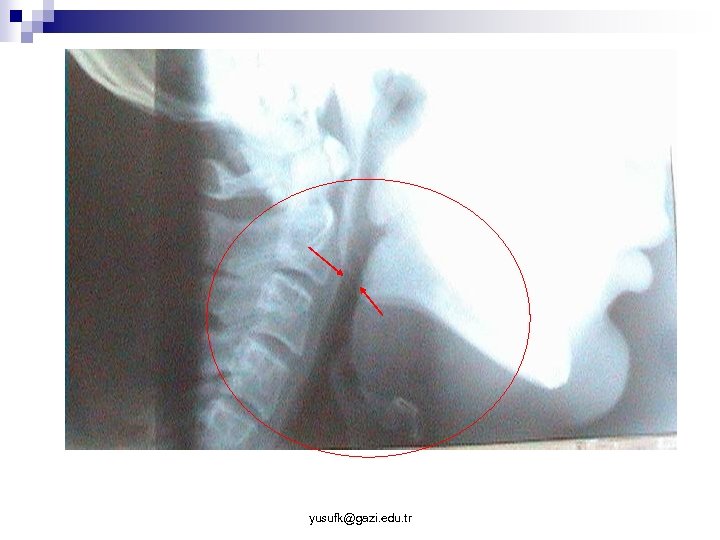

n Dil kökü rezeksiyon cerrahisi ¨ Transservikal dil kökü rezeksiyonu ¨ Intraoral dil kökü rezeksiyonu ¨ (RF n uygulamaları) Dil kökünün kollapsını önleyen operasyonlar ¨ (RF Uygulamaları) ¨ Hyoid n n fiksasyon ameliyatları Thyro-hyoid fiksasyon Hyoid – mandibula fiksasyonu ¨ Sleep-in n tekniği Transservikal glosso-mandibulopeksi yusufk@gazi. edu. tr

Transservikal glossomandibulupeksi Yaş Sex AHI Önceki op. Operasyon Takip Postop AHI ZE 32 M 24. 0 UPPP TGM + THF 16 ay 3. 8 (3. ay) MS 45 M 14. 0 - TGM + UPPP 14 ay 4. 4 (3. ay) KY 41 M 81. 5 Septoplasti TGM + UPPP 14 ay 18. 2 (3. ay) NÇ 56 F 11. 0 LAUP TGM + UPPP 13 ay 3. 2 (3. 5 ay) BSG 43 M 10. 8 - TGM + UPPP 13 ay 17. 9 (4. ay) GS 25 M 76. 8 Nasal cer. (? ) TGM + UPPP 13 ay 16. 2 (4. ay) MO 51 M 11. 1 - TGM + THF 3 (12) ay - İK 29 M 18. 0 Septoplasti TGM + UPPP 3 (12) ay - 30. 9 10. 62 yusufk@gazi. edu. tr 11. 7 (12. ay) CPAP